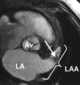

Left atrial ball-valve thrombus